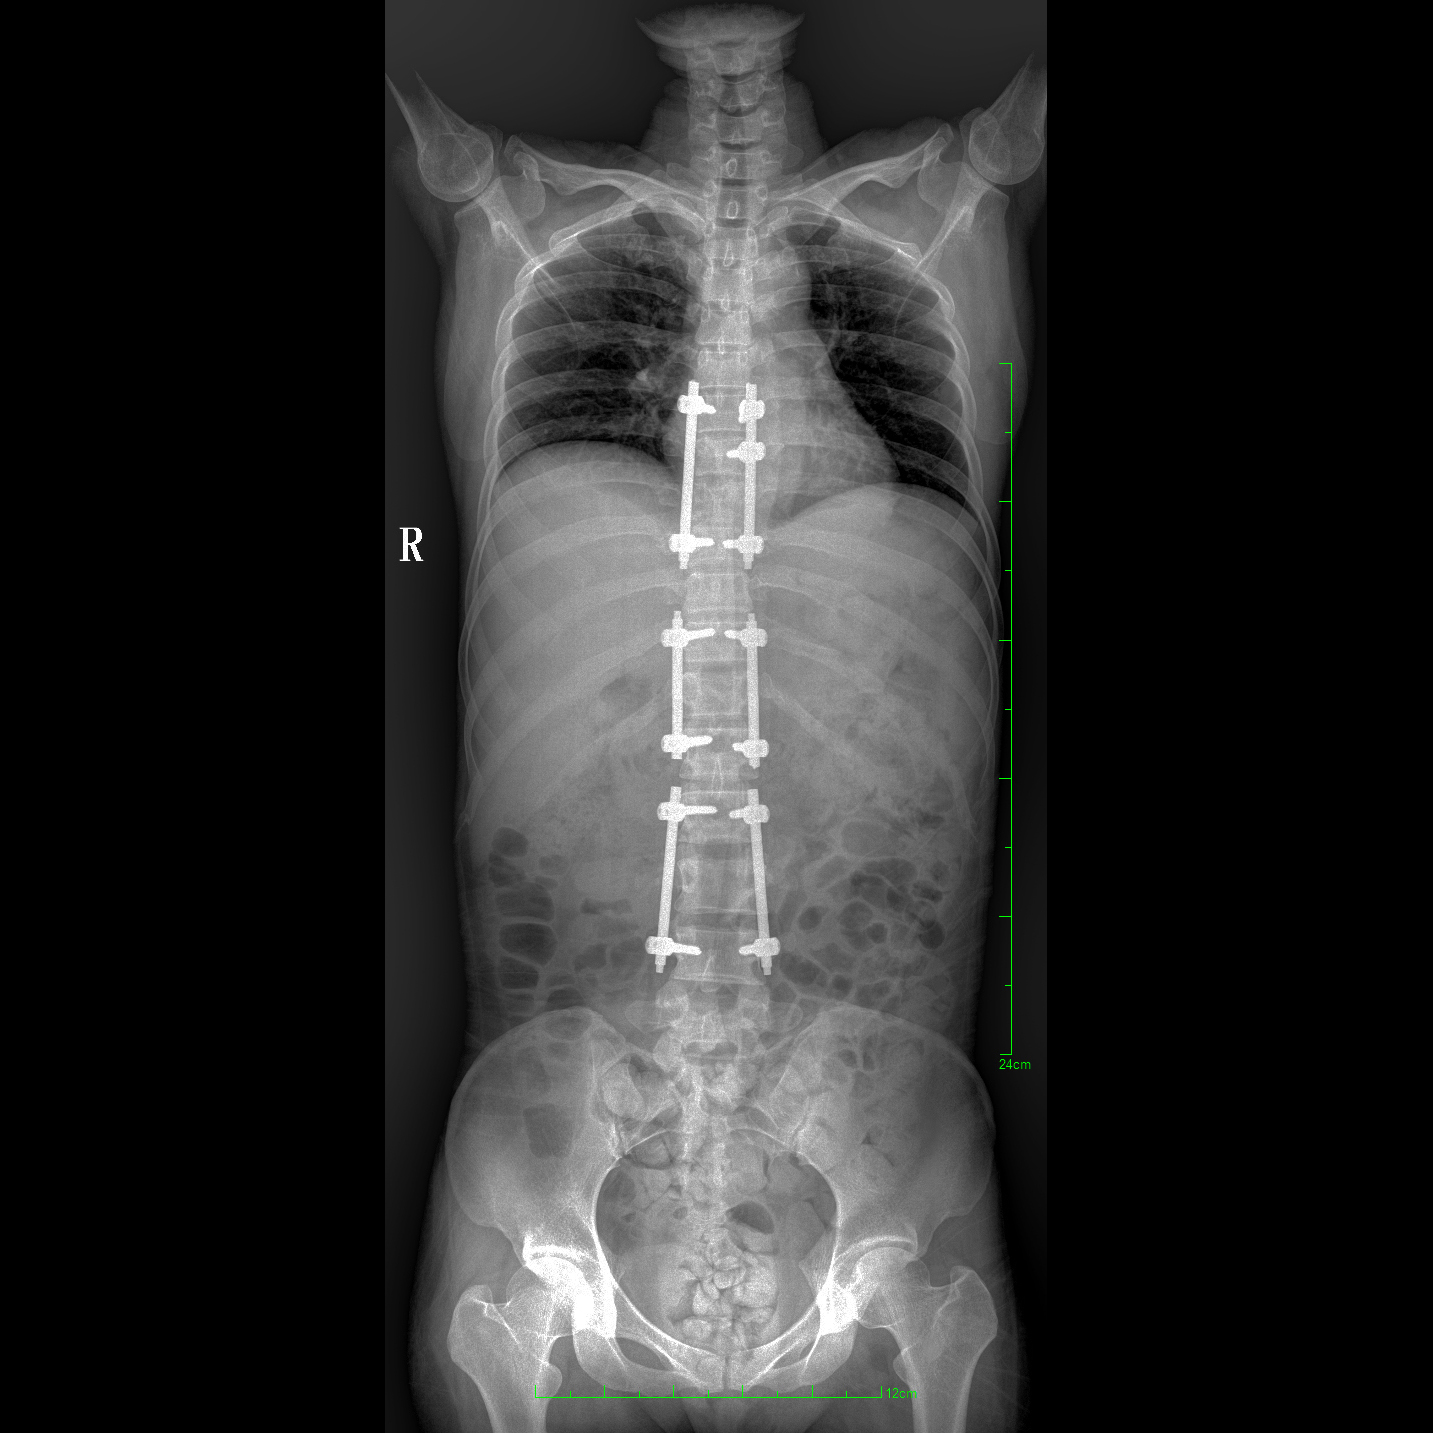

17"*34"有效視野,一次成像不拼接。相較于多張攝影再軟件拼接的DR設(shè)備,PLX8600解決了拼接圖像存在密度不均勻,拼接處圖像配準和放大效應(yīng)等問題,給臨床帶來了大視野影像解決方案,可一次性覆蓋全脊柱或雙下肢影像。

除常規(guī)靜態(tài)攝影外,PLX8600大平板具備動態(tài)透視和點片功能,透視采集功能可支持大視野、多角度的可視化觀察。通過可視化的動態(tài)影像,配合點片功能,能夠很好的觀察復(fù)雜部位病灶,有效的抓取關(guān)鍵幀,降低患者多次攝片的概率。如:全脊柱狀態(tài)評估、長骨關(guān)節(jié)活動度、下肢靜脈造影瓣膜功能評估、消化道功能評估、脊髓造影等更多大視野臨床應(yīng)用。